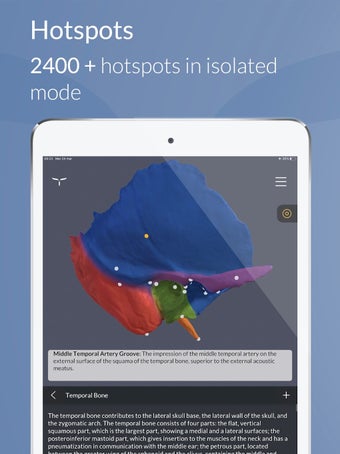

Para ayudar en el aprendizaje y la memorización, la aplicación incluye una vasta colección de textos científicos divididos en tres niveles cognitivos, que van desde una visión general hasta definiciones altamente detalladas.